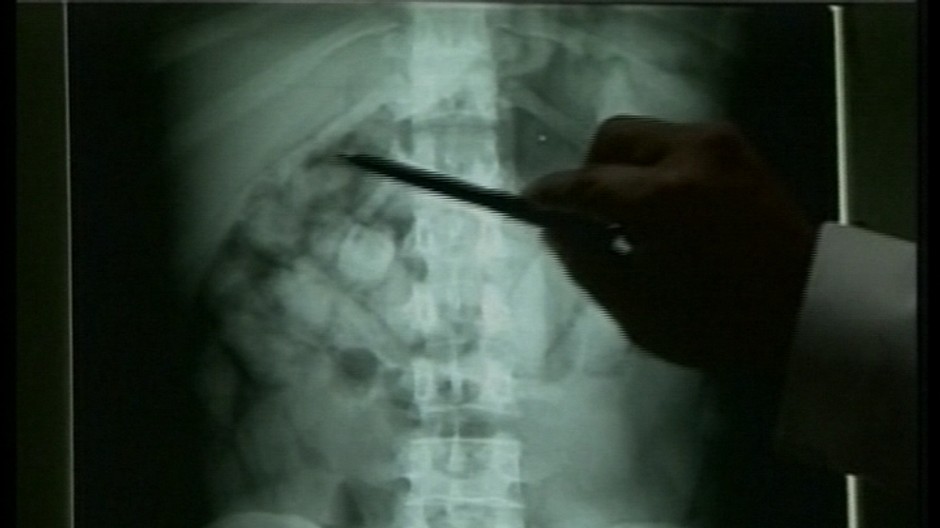

V útrobách tela na všetko odhodlaného politika, ktorého dostala do ťažkej finančnej situácie predovšetkým neúspešná kampaň pred provinčnými voľbami v roku 2007, našli strážcovia poriadku 100 balíčkov kokaínu.